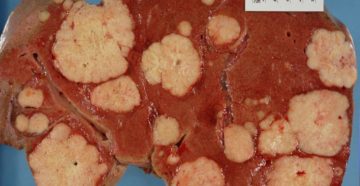

Что такое метастазы? Из-за распада, распространения и активации клеток злокачественного новообразования появляются метастазы при раке….